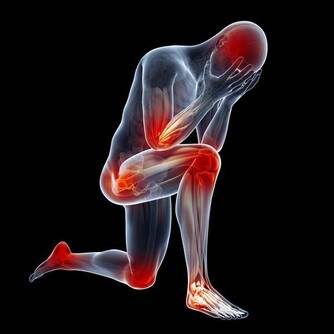

研究發現,高飽和脂肪(存在於動物性食品和全乳製品)和反式脂肪(存在於包裝食品)會對低密度脂蛋白膽固醇產生更大的影響,這些所謂的“壞膽固醇”會造成動脈粥樣硬化。因此,在飲食中避免這兩種脂肪是非常重要的。